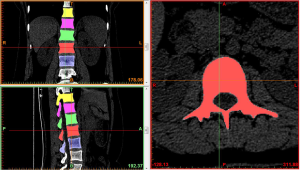

Region growing and edit masks: the segmented regions on the above mask that were not connected to each other were formed into a new mask using region growing. The region growing feature was used to roughly extract various lumbar segments of interest. The boundary contour of each bone on each section of the scanned images was modified or erased to remove the unwanted hip bone portion, so that the boundary contour between bones could be accurately distinguished, especially the upper and lower facet joints (Figures 4,5).

At the end of the tomographic image processing, three-dimensional surface model of the spine and pelvis was reconstructed using the three-dimensional calculation function of the software to generate independent skeletal models of each vertebral body and sacrum in order to clearly and directly reproduce the three-dimensional morphology of the bone structure. The image from the three-dimensional reconstruction could be demonstrated by rotation in all directions and translation. It was also possible to hide, delete, add, and merge the components as needed in this model to obtain different looks and effects (Figure 6).